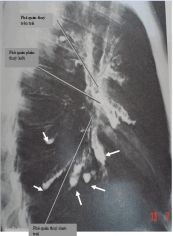

Hình ảnh áp xe phổi phải có mức nước mức hơi trên phim chụp x quang phổi thẳng được thể hiện như thế nào? Mời các bạn tham khảo bài viết dưới đây để hiểu rõ hơn nhé!